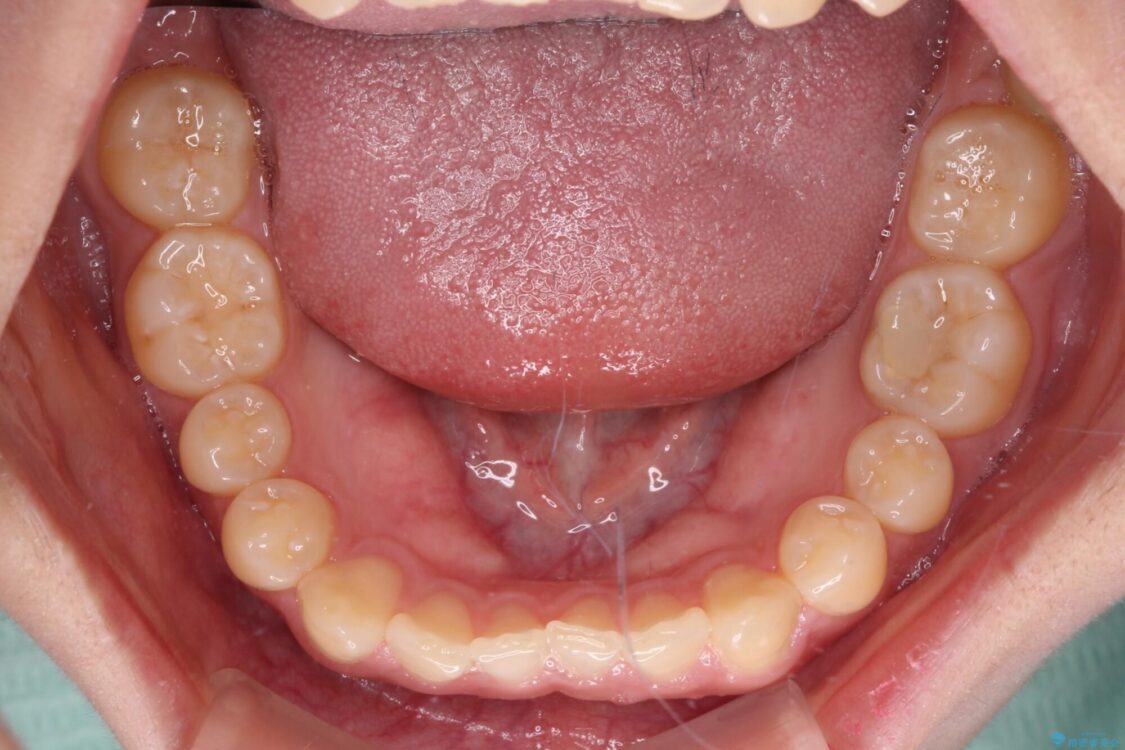

治療途中

• 治療途中の奥歯と矯正治療の後戻り インビザライン・ライトによる矯正治療 治療途中画像